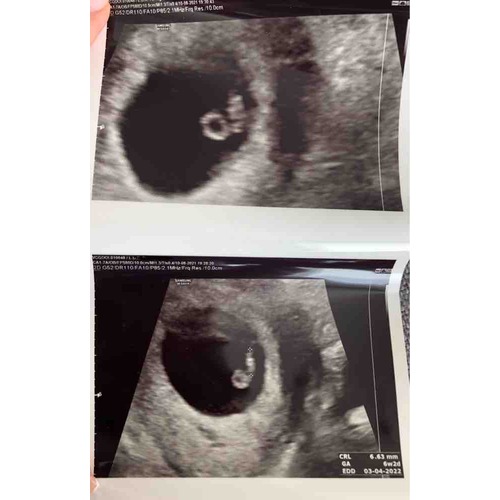

6.5 weekjes, uitwendig! Ben benieuwd 🥰